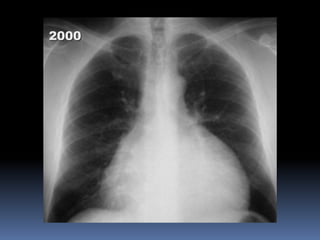

CLINICA [8]

 Normalmente, únicamente una pequeña cantidad de liquido está presente

entre las hojas parietal y visceral del pericardio.

 En ciertas condiciones, este espacio puede ser llenado completamente de

liquido, dando lugar a la efusión pericárdica.

 Debido a que el pericardio fibroso es relativamente fijo, las estructuras no

pueden moverse libremente, una rápida acumulación de líquidos dentro

del saco pericárdico causa compresión del corazón [taponamiento

cardíaco], resultando en fallo biventricular.

 La remoción del liquido en exceso con una aguja insertada hacia el saco

pericárdico puede aliviar los síntomas.

95